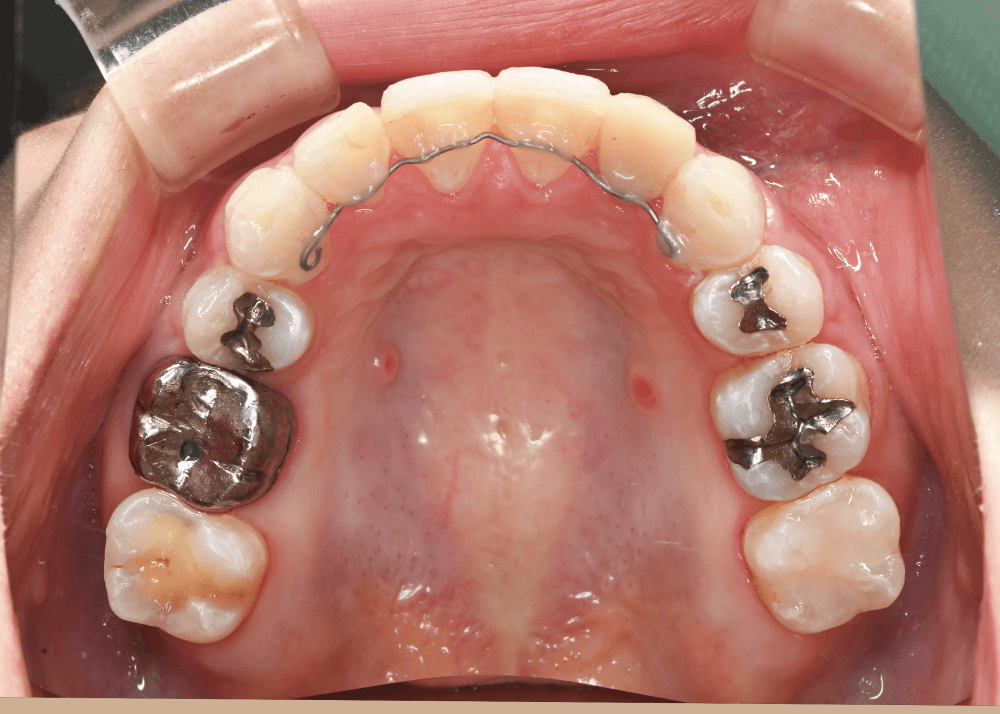

リンガルアーチの併用

歯列全体を前方へ移動させる際には、

アーチ形態を維持するための補助装置としてリンガルアーチを併用しました。

これにより歯列の形を安定させながら、

上下の噛み合わせを維持したまま歯列を前方へ移動させることが可能になります。

治療後の変化

治療後は、舌側に倒れていた前歯の傾きが改善しています。

・上下前歯のなす角(Interincisal angle)

138° → 125°

前歯のポジションが適正化されたことで、スマイル時に奥まって見えていた歯の見え方が改善し、より自然な印象になっています。

また、唇を内側から支える「口唇サポート」が回復し、横顔の印象にも変化がみられました。